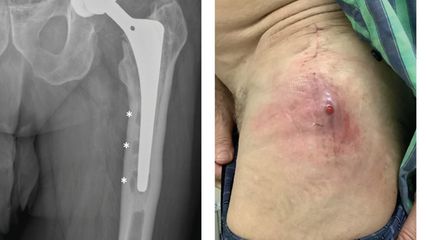

<p class="article-content"><div id="keypoints"> <h2>Keypoints</h2> <ul> <li>Bei bis zu 50 % aller komplexen RM-Nähte finden sich begleitende Läsionen der Subscapularissehne.</li> <li>Traumatische Läsionen der Subscapularissehne sind hingegen oft isoliert.</li> <li>Pathomechanismus sind die forcierte Flexion und Aussenrotation in Abduktion.</li> <li>Die transtendinöse Technik mit zusätzlicher lateraler Suture-Bridge gewährt eine hohe mechanische Stabilität.</li> <li>Bei retrahierten Rupturen sind die Identifikation und Reposition des «Kommazeichens» essenziell; diese kräftige ligamentäre Verbindung zwischen dem Oberrand der Subscapularissehne und dem Vorderrand der Supraspinatussehne verleiht dem endgültigen Konstrukt zusätzliche Stabilität.</li> <li>Die beschriebene Technik garantiert einen flüssigen, reproduzierbaren Ablauf.</li> <li>Das Herstellen eines «Fensters » lateral der Korakoidspitze erleichtert das Fadenmanagement.</li> <li>Die Optik verbleibt bei unserer Technik im dorsalen Standardportal. Druck auf den Humeruskopf nach dorsal vergrössert den zur Verfügung stehenden Raum.</li> </ul> </div> <h2>Häufigkeit, Anatomie und Pathomechanismus</h2> <p>Die Häufigkeit von Läsionen der Subscapularissehne wurde lange ungerechtfertigterweise unterschätzt. Bei bis zu 30 % aller Schulterarthroskopien bzw. bis gegen 50 % aller arthroskopischen Rekonstruktionen von Massenrupturen der RM finden sich begleitende Verletzungen der Subscapularissehne.<sup>1, 2</sup> Dies hat entscheidende Relevanz, da der Subscapularismuskel als kräftigster Muskel der RM der zentrale ventrale Kraftvektor und somit essenziell für das biomechanisch wichtige anteroposteriore «force-coupling» ist. Er balanciert die nach posterior wirkende Infraspinatusmuskulatur und ist somit Fundament jeder physiologischen Schulterfunktion.<br /><br /> Der Footprint der Subscapularissehne ist in einen sehnigen proximalen Part und einen muskulösen distalen Part unterteilt und gleicht in seiner Form einem «Komma» resp. einem «menschlichen Ohr».<sup>2, 3</sup> Das Ausmass des kranialen tendinösen Footprints beträgt ca. 2,5cm; die kaudale muskuläre Insertionsstelle misst ca. 1,5cm und zeigt sich in der Regel intakt.<sup>3, 4</sup> Eine desinserierte Subscapularissehne hat aufgrund ihrer biomechanischen Schlüsselrolle sowie als wichtiger Bestandteil des sogenannten «exposed footprint» (EFP), welcher die Ausdehnung der rupturierten Gesamt-RM definiert, prognostische und klinische Relevanz, sodass wir die Indikation zur Subscapularis-Refixierung konsequent stellen.<sup>2</sup><br /><br /> Burkhart et al. publizierten als Erste eine arthroskopische Technik zur Subscapularis- Refixierung.<sup>5, 6</sup> Seither ist die anatomische Landmarke des «Kommazeichens » integraler Bestandteil jeder Reposition der Subscapularissehne bei retrahierten Rupturen.<sup>6</sup> Das Kommazeichen stellt eine kräftige Gewebebrücke zum Vorderrand der Supraspinatussehne dar, deren Erhaltung die stabile Refixierung der Subscapularissehne stark erleichtert.<sup>5</sup> Das Kommazeichen ist bei retrahierten Rupturen oft im «leeren» Rotatorenintervall zunächst nicht erkennbar, da es sich auf Glenoidniveau befindet. Wenige Präparationsschritte erlauben jedoch dessen Identifikation und das Anschlingen mit einem Haltefaden.<br /> Traumatische Subscapularisrupturen sind wenn möglich rasch zu versorgen, da der Muskel schnell atrophieren kann.<sup>4</sup> Zur Klassifizierung verwenden wir die Einteilung nach Lafosse.<sup>1</sup> Diese Läsionen präsentieren sich oft als isolierte Rupturen ohne wesentliche Beteiligung der posterosuperioren RM, hingegen ist das Biceps- Pulley regelmässig zerstört. Unfallmechanismus ist die forcierte Hyperextension oder die Aussenrotation des abduzierten Arms.<sup>7</sup> Die Mehrheit dieser Rupturen sind klein bis mittelgross mit einem EFP von 1–2cm (Typ Lafosse 2–3) und in der Regel einfach mit einem doppelt bis dreifach armierten Fadenanker zu versorgen. Komplette retrahierte Rupturen, die eine extensive Mobilisierung erforderlich machen, sind im Setting einer traumatischen Rupturgenese seltener und werden in unserer Routine mit zwei doppelt armierten Fadenankern versorgt (Abb. 1).</p> <p><img src="/custom/img/files/files_datafiles_data_Zeitungen_2018_Leading Opinions_Ortho_1803_Weblinks_s36_abb1.jpg" alt="" width="684" height="1082" /></p> <h2>Operationstechnik</h2> <p>Unsere Operationstechnik der traumatischen (und analog auch der degenerativen) Subscapularissehnenruptur erfolgt in 7 Schritten:</p> <ol> <li>Für das Anfrischen des Footprints, die Ankerinsertion sowie das spätere Fadenmanagement benutzen wir das anterosuperiore Portal (ASP), welches wir mit einer Arbeitskanüle versorgen. Ein zusätzlicher perkutaner anteroinferiorer Zugang hilft, mit dem Penetrator oder dem Cleverhook im späteren Verlauf die Subscapularissehne an der richtigen Stelle zu perforieren (Abb. 2).</li> <li>Die lange Bizepssehne ist oft pathologisch verändert bzw. instabil und versperrt den Zugang zum Subscapularis. Sie wird routinemässig in doppelter Loop-Technik mit 2 Orthocord<sup>®</sup>-Fäden mithilfe eines Push-Lock-Ankers 3,5mm am Eingang in den Sulcus bicipitalis epiossär tenodesiert.</li> <li>Bei retrahierten Rupturen wird das Kommazeichen identifiziert und mithilfe der Spectrum-Hohlnadel mittels PDSFaden angeschlungen. Durch lateralen Zug wird die Subscapularissehne angespannt, sodass ein progressiver Release erfolgen kann, bis sich die Sehne spannungslos reponieren lässt (Abb. 3).</li> <li>Ein ventrales Kapselrelease erfolgt mittels Hochfrequenzelektrode entlang der Glenoidkante mit grosszügiger Inzision des verdickten mittleren glenohumeralen Ligaments.</li> <li>Danach erfolgen die Präparation des Rotatorenintervalls unter Release des korakohumeralen Bandes sowie die Darstellung der Korakoidspitze und des Aussenrandes der «conjoined tendon». Ein hier grosszügig angelegtes «Fenster », in das wir eine Passport-Kanüle einlegen, erleichtert das störungsfreie Fadenmanagement und Knoten auf der reponierten Subscapularissehne ohne Gewebebrücken.</li> <li>Anfrischen des knöchernen Footprints am Tuberculum minus mit dem Shaver über das ASP. Danach Eindrehen eines – je nach Ausdehnung der Ruptur – 2–3-fach armierten Fadenankers.</li> <li>Sehnenperforation mit dem Cleverhook. Wir wählen eine Mason-Allen- Konfiguration mit horizontaler Matratzennaht und vertikalem, die Naht quasi umschliessendem «simple stich», wobei der kranialste Faden die Sehne nicht perforiert, sondern auf dem Oberrand des Subscapularis zu liegen kommt. Anschliessendes Knoten. Ein Fadenpaar wird für die Suture-Bridge nach lateral belassen, wodurch das Kommazeichen wirksam «verblockt» wird (Abb. 4, 5).</li> </ol> <p><img src="/custom/img/files/files_datafiles_data_Zeitungen_2018_Leading Opinions_Ortho_1803_Weblinks_s36_abb2_3_4_5.jpg" alt="" width="1417" height="1592" /></p> <h2>Nachbehandlung</h2> <p>Die Nachbehandlung erfolgt nach unserem standardisierten Schema mit relativer Immobilisierung im Ultrasling für 6 Wochen. In dieser Zeit sind Pendelübungen sowie Rotationsübungen mit dem Stab im unteren Quadranten erlaubt. Die Aussenrotation soll jedoch auf maximal 0–10° limitiert bleiben. Nach 6 Wochen erfolgt dann die aktiv-assistive Beübung der operierten Schulter mit sukzessiver Steigerung der Aussenrotation.</p></p>